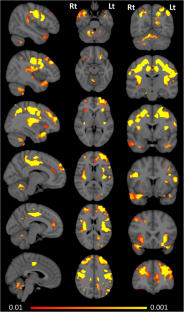

Primary lateral sclerosis (PLS) is classically considered a ‘pure’ upper motor neuron disorder. Motor cortex atrophy and pyramidal tract degeneration are thought to be pathognomonic of PLS, but extra-motor cerebral changes are poorly characterized. In a prospective neuroimaging study, forty PLS patients were systematically evaluated with a standardised imaging, genetic and clinical protocol. Patients were screened for ALS and HSP associated mutations, as well as C9orf72 hexanucleotide repeats. Clinical assessment included composite reflex scores, spasticity scales, functional rating scales, and screening for cognitive and behavioural deficits. The neuroimaging protocol evaluated cortical atrophy patterns, subcortical grey matter changes and white matter alterations in whole-brain and region-of-interest analyses. PLS patients tested negative for known ALS- and HSP-associated mutations and C9orf72 repeat expansions. Voxel-wise analyses revealed anterior cingulate, dorsolateral prefrontal, insular, opercular, orbitofrontal and bilateral mesial temporal grey matter changes and white matter alterations in the fornix, brainstem, temporal lobes, and cerebellum. Significant thalamus, caudate, hippocampus, putamen and accumbens nucleus volume reductions were also identified. Extra-motor clinical manifestations were dominated by verbal fluency deficits, language deficits, apathy and pseudobulbar affect. Our clinical and radiological evaluation confirms considerable extra-motor changes in a population-based cohort of PLS patients. Our data suggest that PLS should no longer be considered a neurodegenerative disorder selectively affecting the pyramidal system. PLS is associated with widespread extra-motor changes and manifestations which should be carefully considered in the multidisciplinary management of this low-incidence condition.